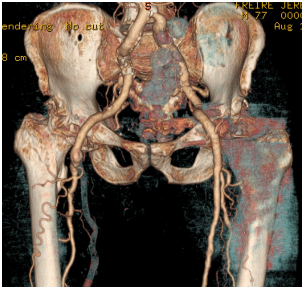

It is a male patient, who is currently 83 years old, followed in outpatient orthopedics since 2002 because of bilateral coxarthrosis. In 2003 he underwent left total hip arthroplasty uncomplicated, with good functional outcome and regression of symptoms (Figure 1).

Figure 1 Pre-operative X-Ray.

In 2004 while preparing for right THA, it was identified thrombosed aneurysm of the right popliteal artery in need of carrying out femoral-popliteal bypass. Because of this major vascular event, the right hip arthroplasty has been successively delayed until 2012. At this time, and after balancing the risks and benefits, was decided to perform a right cemented THA. The surgery and the postoperative elapsed normally without any adverse vascular, orthopedic or neurologic events (Figure 2).

Figure 2 Post-operative X-Ray.